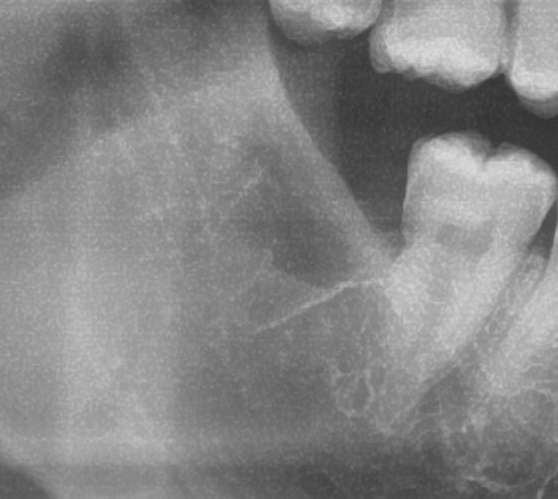

次にパノラマ写真を撮影してみると、右下の親知らずは手前の歯の歯を押すように少し斜めに生えているのが確認できました。